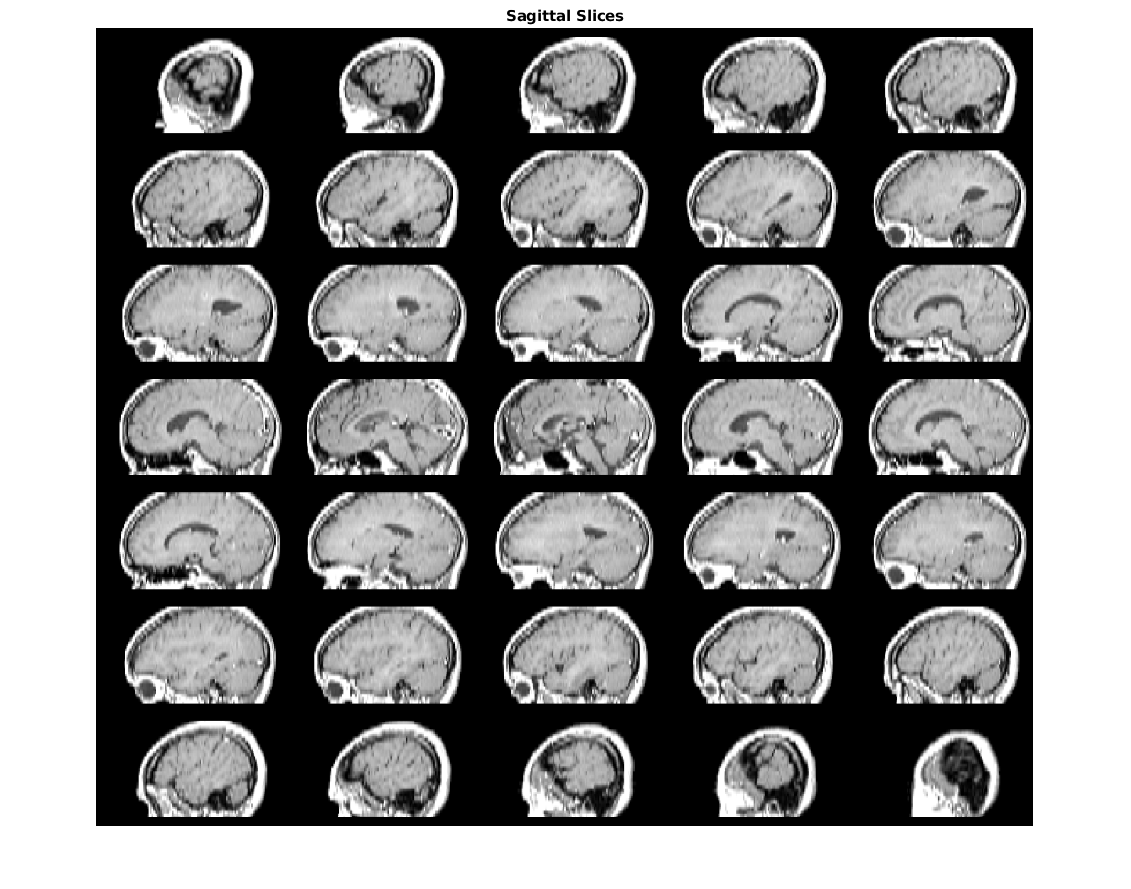

Slices contains

Slices contains 142 фотографий